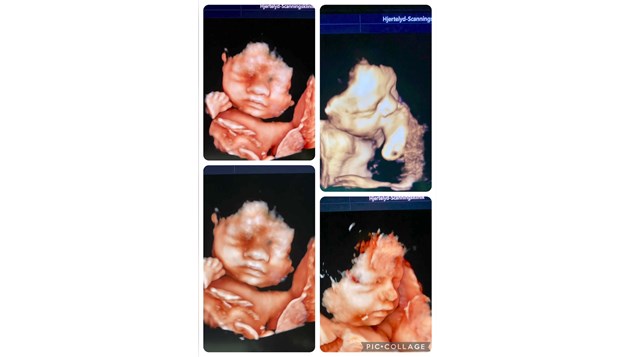

Den sødeste lillebror på besøg i klinikken.

Han er 34 uger og vejer ca 2240 gram i dag.

Han trives i maven; bevægelser, vandmængde og blodgennemstrømning i navlesnoren siger, at han trygt og godt stiler mod en vægt på 3400-3500 gram uge 40.

Forventningsfulde forældre glæder sig til ankomsten af sund og voksende baby i uge 40